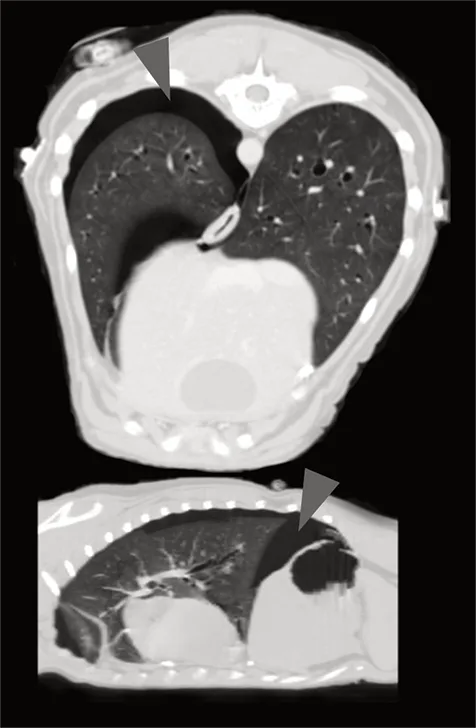

Axial and sagittal CT scan showing pneumothorax (arrowheads) in a dog following motor vehicle blunt trauma